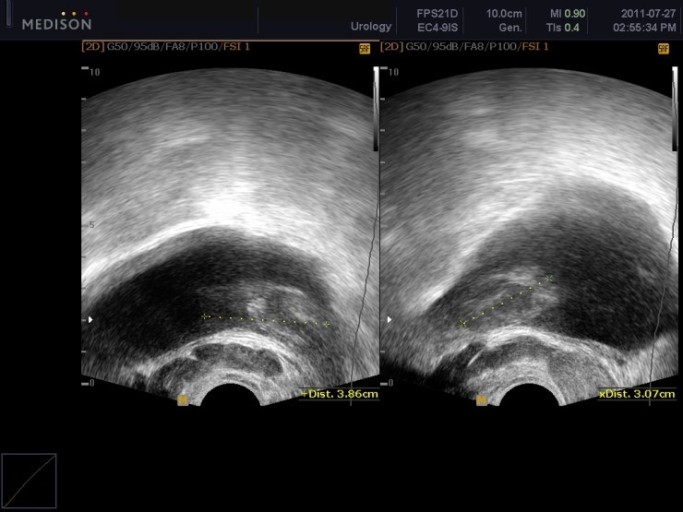

전립선암은 초기에는 특별한 증상이 없어 '침묵의 암'이라고 불리지만, 일단 증상이 나타나기 시작하면 삶의 질에 큰 영향을 미칩니다. 특히 초기 증상은 양성 질환인 전립선 비대증과 매우 유사하여 혼동하기 쉽기 때문에 더욱 주의 깊게 살펴봐야 합니다.

전립선암은 주로 전립선의 바깥쪽 부분인 말초대(Peripheral Zone)에서 발생합니다. 이 때문에 종양이 요도를 압박할 정도로 커지기 전까지는 증상이 나타나지 않는 경우가 많지만, 아래와 같은 비뇨기계 증상 및 전신 증상이 나타나기 시작하면 반드시 정밀 검사가 필요합니다.